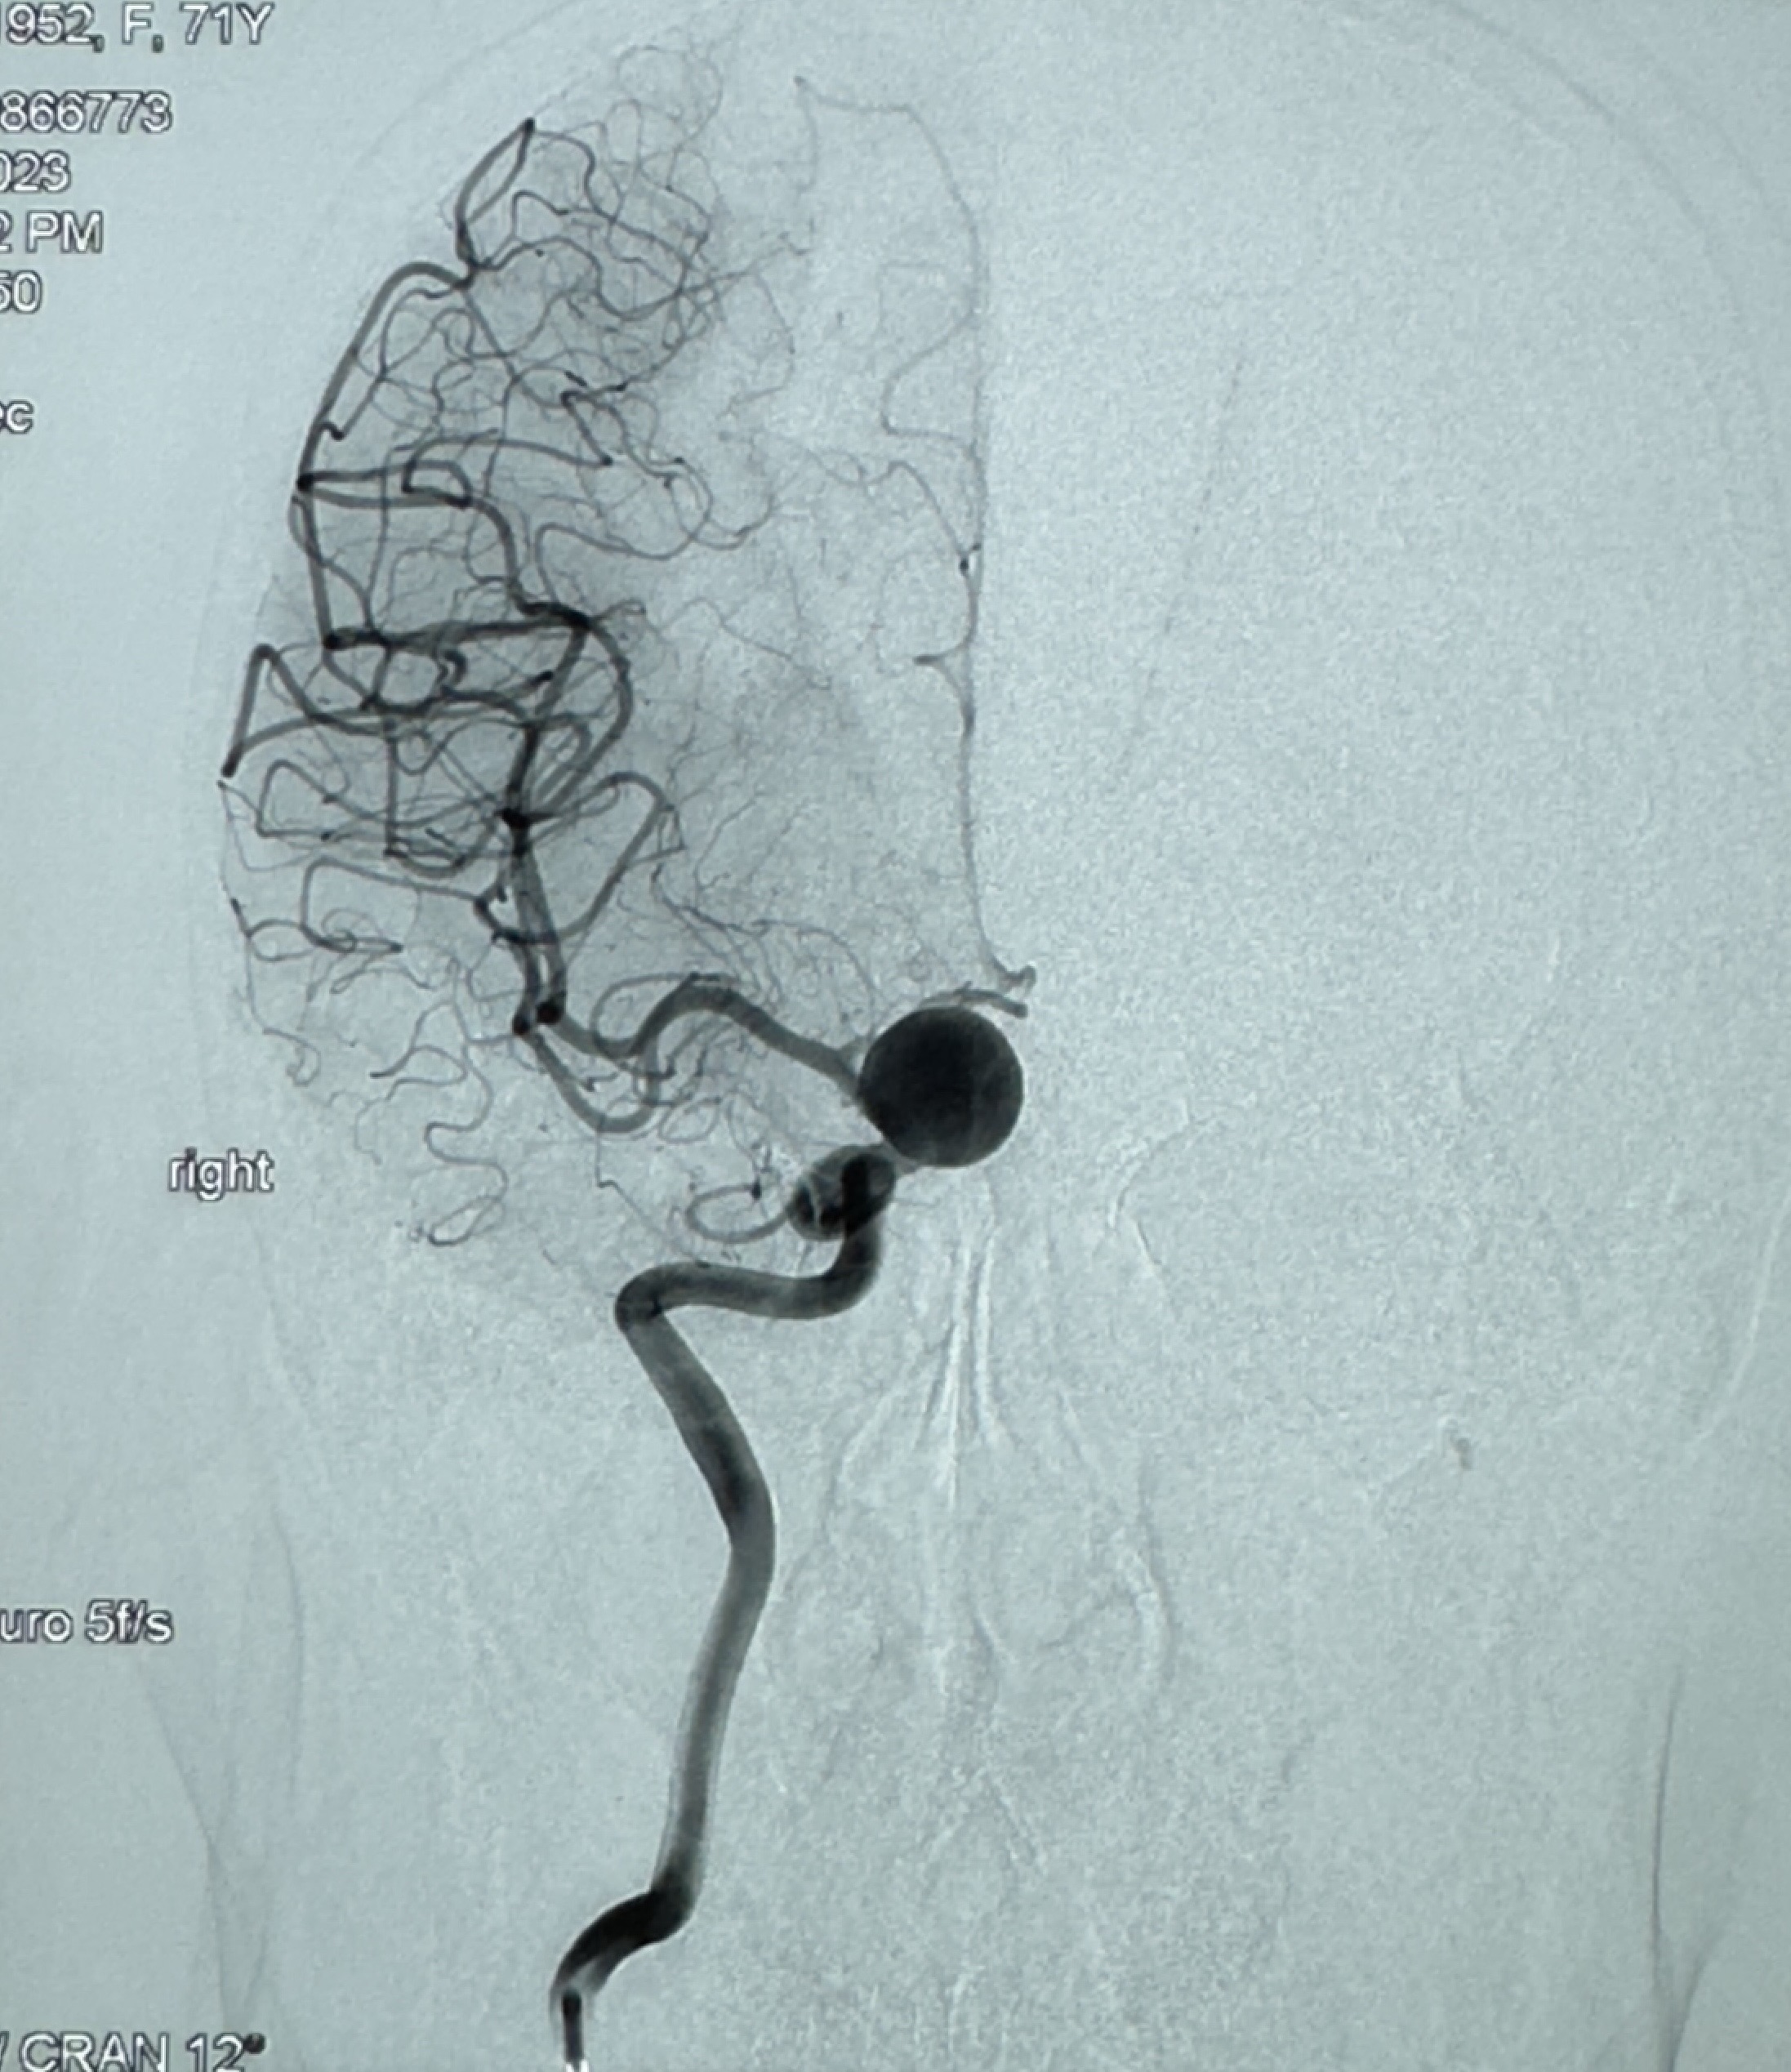

2023-12-08 复旦大学附属华山医院 全脑血管造影:右侧颈内动脉C6段动脉瘤,瘤颈6.68mm,动脉瘤大小13.28*12.34mm

2023-12-08外院DSA:右侧颈眼动脉瘤,约13*12mm大小,压颈试验显示左右向及后向前代偿可

测量动脉瘤的大小:16*13.8*7.6mm大小,较原先变大,考虑双抗后瘤内血栓溶解可能